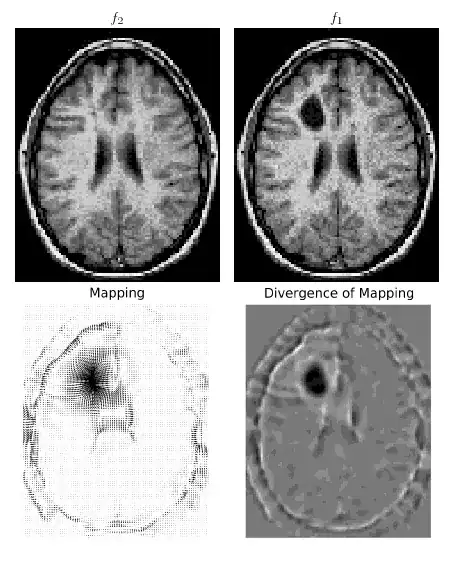

The paper can be summarized as follows :

- find an initial map $u$ using 1D histogram matchings along the x and y coordinates

- solve for the fixed point of $u_t = \frac{1}{\mu_0} Du \nabla^\perp\triangle^{-1}div(u^\perp)$ , where $u^\perp$ stands for a 90 degrees counter clockwise rotation, $\triangle^{-1}$ for the solution of the poisson equation with Dirichlet boundary conditions (=0), and $Du$ is the determinant of the Jacobian matrix.